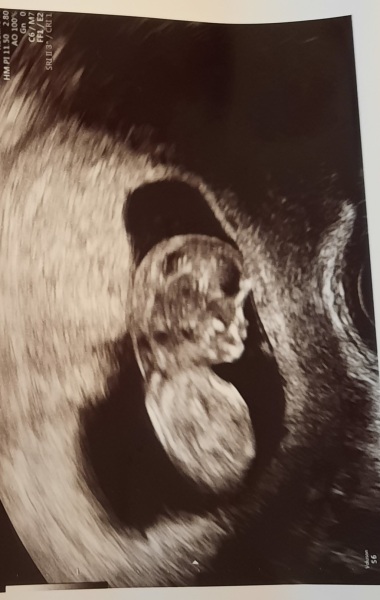

rosyday · 22/12/2022 17:36

Same as you, I also went for an early scan today and I'm so happy we did. It was my first one and it was just so reassuring to see the baby and hear the heartbeat ❤️

The sonographer dated me as 9 weeks so a bit further on than I thought- that has moved up my due date to 27 July 😊